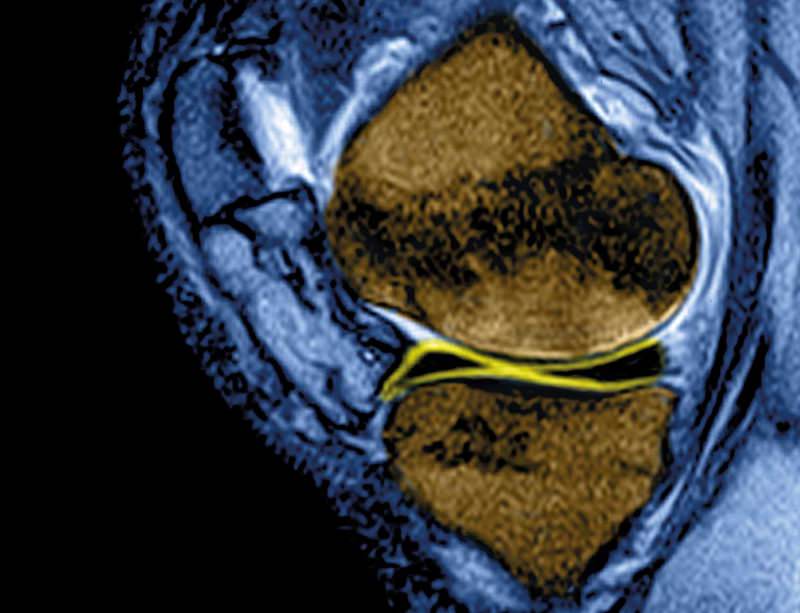

Articular Cartilage in the Knee Current MR Imaging Techniques and Knee Cartilage Breakthrough damaged cartilage can be treated through a technique called microfracture, in which tiny holes are drilled in the surface of a joint. hyalex orthopaedics, inc., announced that the hyalex® cartilage system has been granted breakthrough device designation from the u.s. at the first inkling of a creaky knee, patients could get a single shot in the joint. Knee Cartilage Breakthrough.

H & E staining of knee articular cartilage. Osteoarthritic degradation Knee Cartilage Breakthrough damaged cartilage can be treated through a technique called microfracture, in which tiny holes are drilled in the surface of a joint. The hyalex cartilage system is intended to repair cartilage defects and restore function for patients with loss of knee articular cartilage and bone requiring surgery. natural cartilage can withstand a whopping 5,800 to 8,500 pounds per. Knee Cartilage Breakthrough.

(PDF) Interactive knee cartilage extraction using efficient Knee Cartilage Breakthrough Discovered within the novartis institutes for biomedical. a phase iib study in patients with knee oa is underway. damaged cartilage can be treated through a technique called microfracture, in which tiny holes are drilled in the surface of a joint. natural cartilage can withstand a whopping 5,800 to 8,500 pounds per inch of tugging and squishing,. Regrowing. Knee Cartilage Breakthrough.